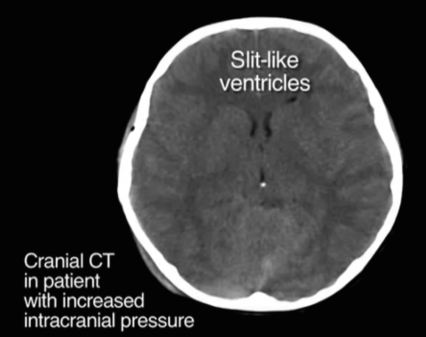

Increased Intracranial Pressure

- Concerning CT findings include4

- Midline shift

- Loss of normal cisterns and ventricles

- Ask yourself: are there any black fluid filled spaces in the brain that are missing on this CT?